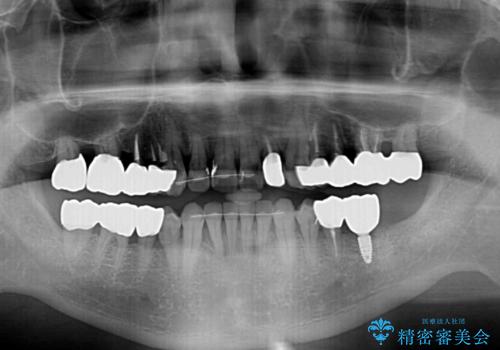

歯列不正と歯周病 総合歯科治療による全顎治療

- 前歯がのデコボコや、奥歯に咬んだときに痛みがあるとのことで来院された患者様です。

全体的に問題が多く、全てをしっかりと治療したいとのことでした。

全体的に中等度の歯周病と診断されたため、歯周外科処置やインプラントによる咬合回復から進めて行き、矯正治療による歯列改善を行った後にオールセラミッククラウンにて補綴することとしました。

歯槽骨の再生治療を行ったため、外科処置後の静置期間がながくなり、4年弱の治療期間となりました。

初診来院時には矯正治療を行うことは想像していなかったようで、治療後には咬みやすさだけでなく、前歯が大変審美的に仕上がり、患者様には大変満足していただきました。